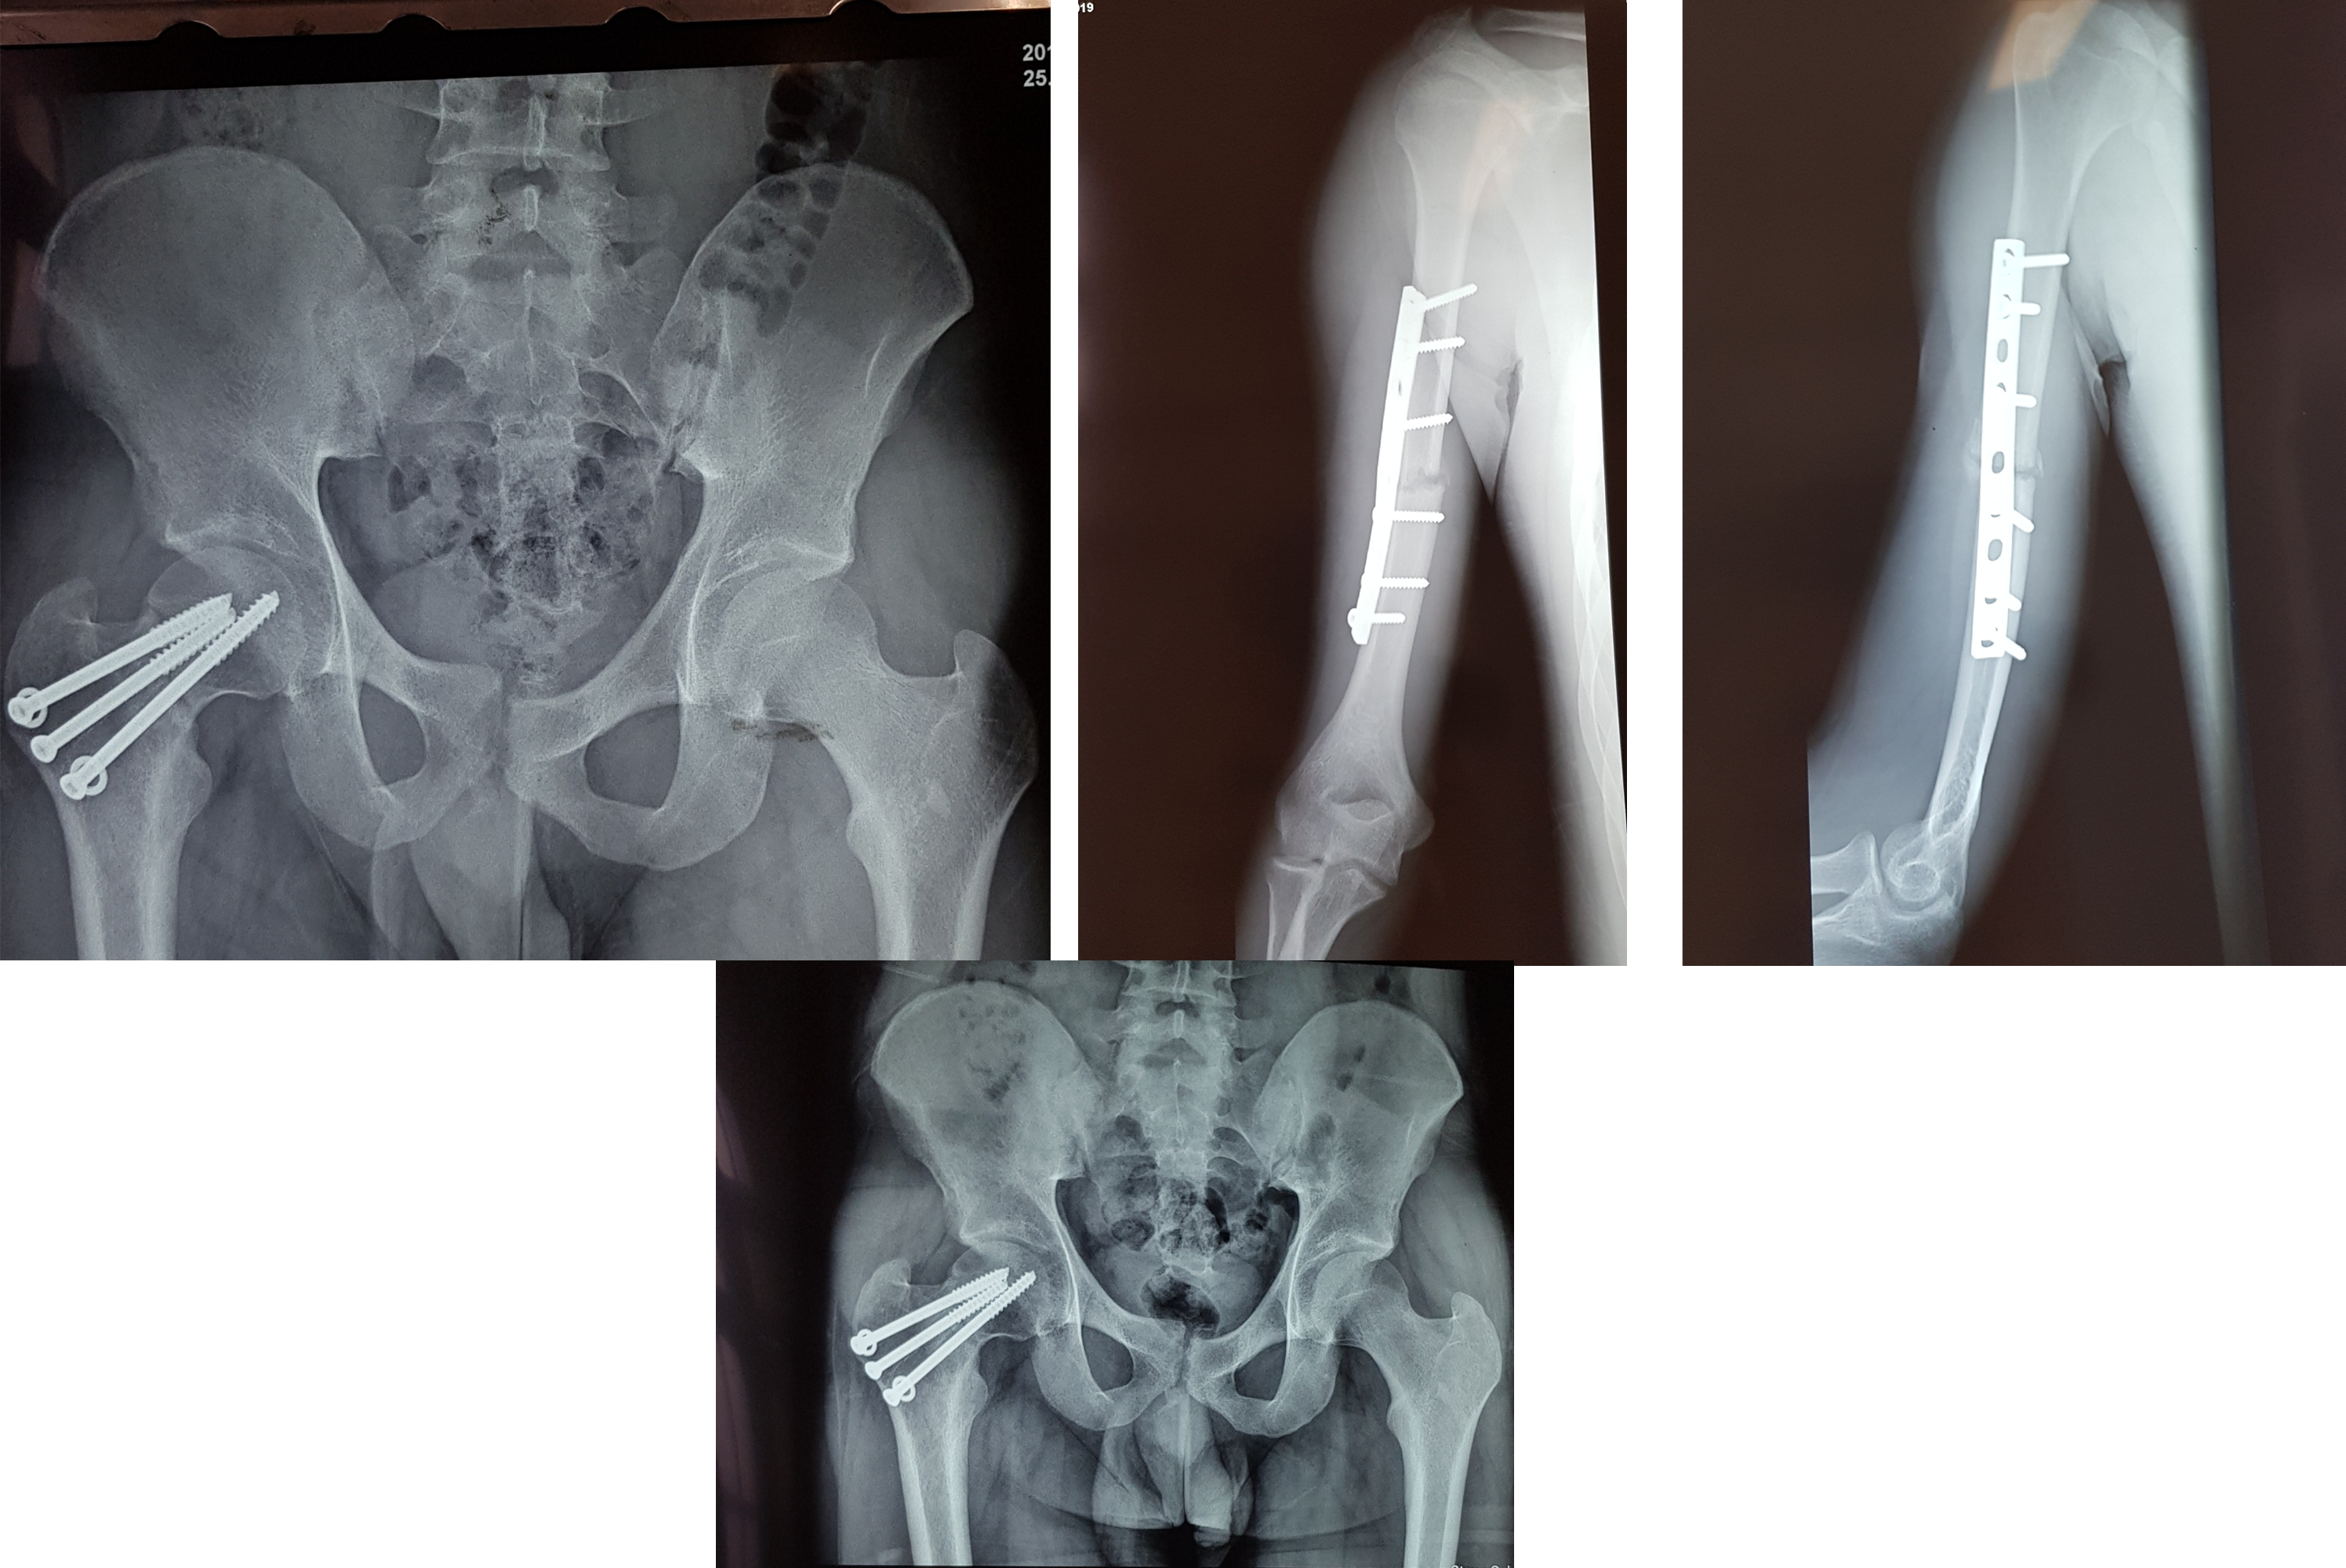

FRACTURA DE CADERA Y HÚMERO DERECHO